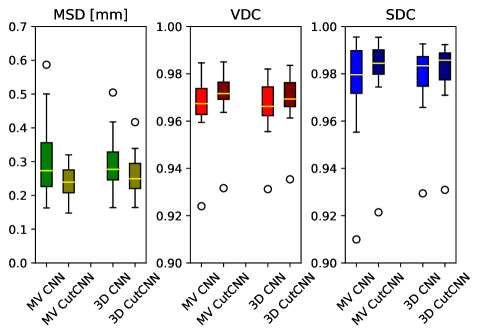

22 scans were randomly selected as test subjects for the experiment, leaving 177 skulls for model training. Using convolutional kernels of size 3 in all the CNN models results in the 3D model having the same number of trainable parameters as the sum of the three orthogonal 2D models. The comparison between the MV ensemble and the 3D approach can therefore be considered an ablation study to an extent. CutCNN models also have a similar number of parameters, the only difference being the final edge probability output layer. Quantitative comparison of results of each method are presented in Figure 4 and Table 1. Further qualitative results are shown in Figure 5 and 1.

CutCNN segmentation framework resulted in a performance gain in all cases in terms of every metric used in the experiment over standard CNN approaches. The output of CNN object probability map often contains errors near external objects or smaller tissue defects as these are scarce in the training data distribution. However, the graph-cut optimization guides the resulting binary segmentation towards a spatially consistent and compact shape, often eliminating these artifacts if a detected edge corresponds mostly to the correct object boundary. This effect is further illustrated in Fig. 1.

Our second observation is that using 3D convolutional kernels has a rather small effect on the final segmentation precision quantitatively compared to the MV approach. However, although the quantitative difference is small, for applications in medical additive manufacturing, it is important to avoid ragged segmentation output which may result from MV CNN in areas of lower model certainty. These include for example teeth, which are challenging to detect, especially when the lower and upper teeth are in contact (see Figure 5 a), or maxillary sinus, which is often enclosed in order to improve mechanical stability of the manufactured model (see Figure 5 b). Therefore, 3D U-nets are often considered necessary to avoid these discontinuities caused by slice-by-slice processing.

However, this artifact can also be addressed by employing the CutCNN framework since ragged segmentation boundary introduces a high boundary-term penalization during optimization and it is therefore avoided in the final binary segmentation. Thus, employing CutCNN allows the decision between 3D or multi-view approach to be merely a technical choice. Using 2D models can offer some advantages, such as faster training of deeper models with less overfitting [10].

We also evaluate the performance of the proposed method in the context of existing related work in skull segmentation. In terms of volumetric Dice coefficient, the proposed method achieved performance of in the multi-view scenario and in the 3D scenario. This result is considerably higher than that of reported by Minnema et al. [11]. This is probably caused by the lower resolution in our experiments and by several limiting factors in the other works, including the small training set that only allowed for a smaller CNN architecture and employing a patch-based approach. To our best knowledge, the presented work is the first to apply a fully automatic segmentation approach to a pathological skull dataset of this size. Furthermore, we also achieve a low mean surface distance with the proposed method, namely mm.